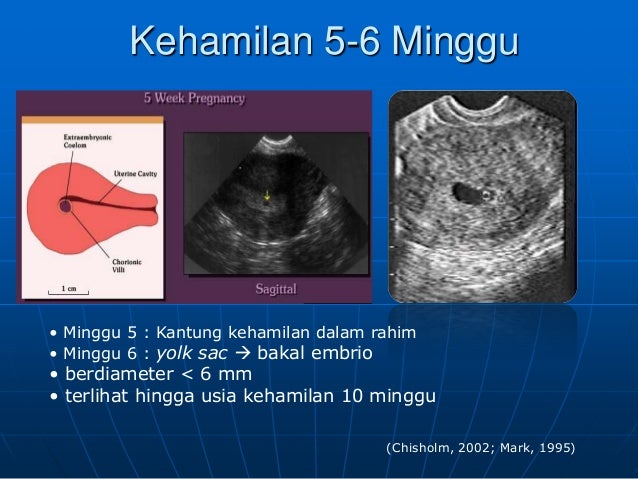

BILIK SONOGRAFER : Kehamilan Awal (Kehamilan Trimester 1)

Gambaran Hasil Usg Kehamilan 5 Minggu Yang Perlu Diperhatikan - Hamil.co.id

Gambaran Hasil Usg Kehamilan 5 Minggu Yang Perlu Diperhatikan - Hamil.co.id

USG dasar dalam kehamilan

USG dasar dalam kehamilan

USG dasar dalam kehamilan

USG dasar dalam kehamilan